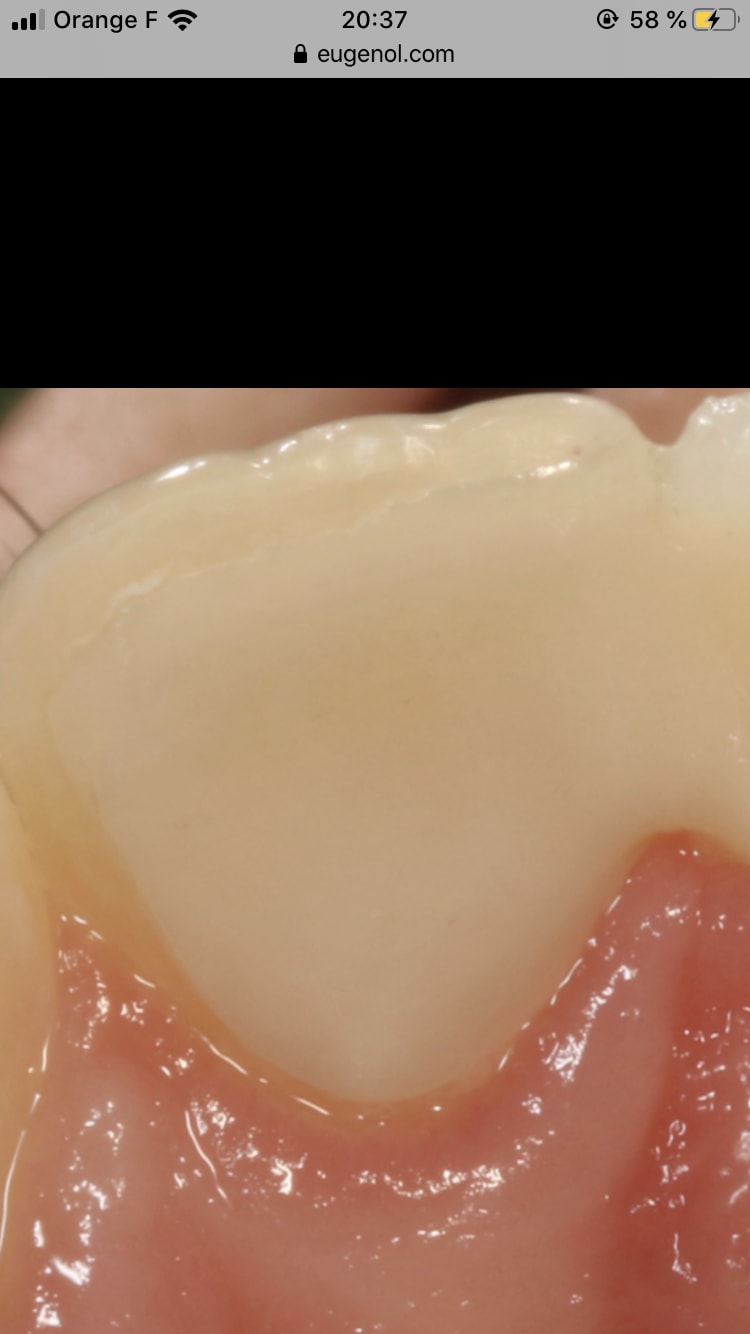

Plus le boîtier de connexion entre facette et élément inter est épais et plus la prothèse est solide, faudrait être idiot pour affiner cette zone et se priver les crêtes marginales mésiales de 11 et 21, ces crêtes sont présentes et fonctionnelles (la photo miroir plein flash sur la face palatine écrase les volumes je te l’accorde)

La Crête discale de la 21 n’est pas concernée par la préparation (voir plâtre), donc elle est aussi présente.